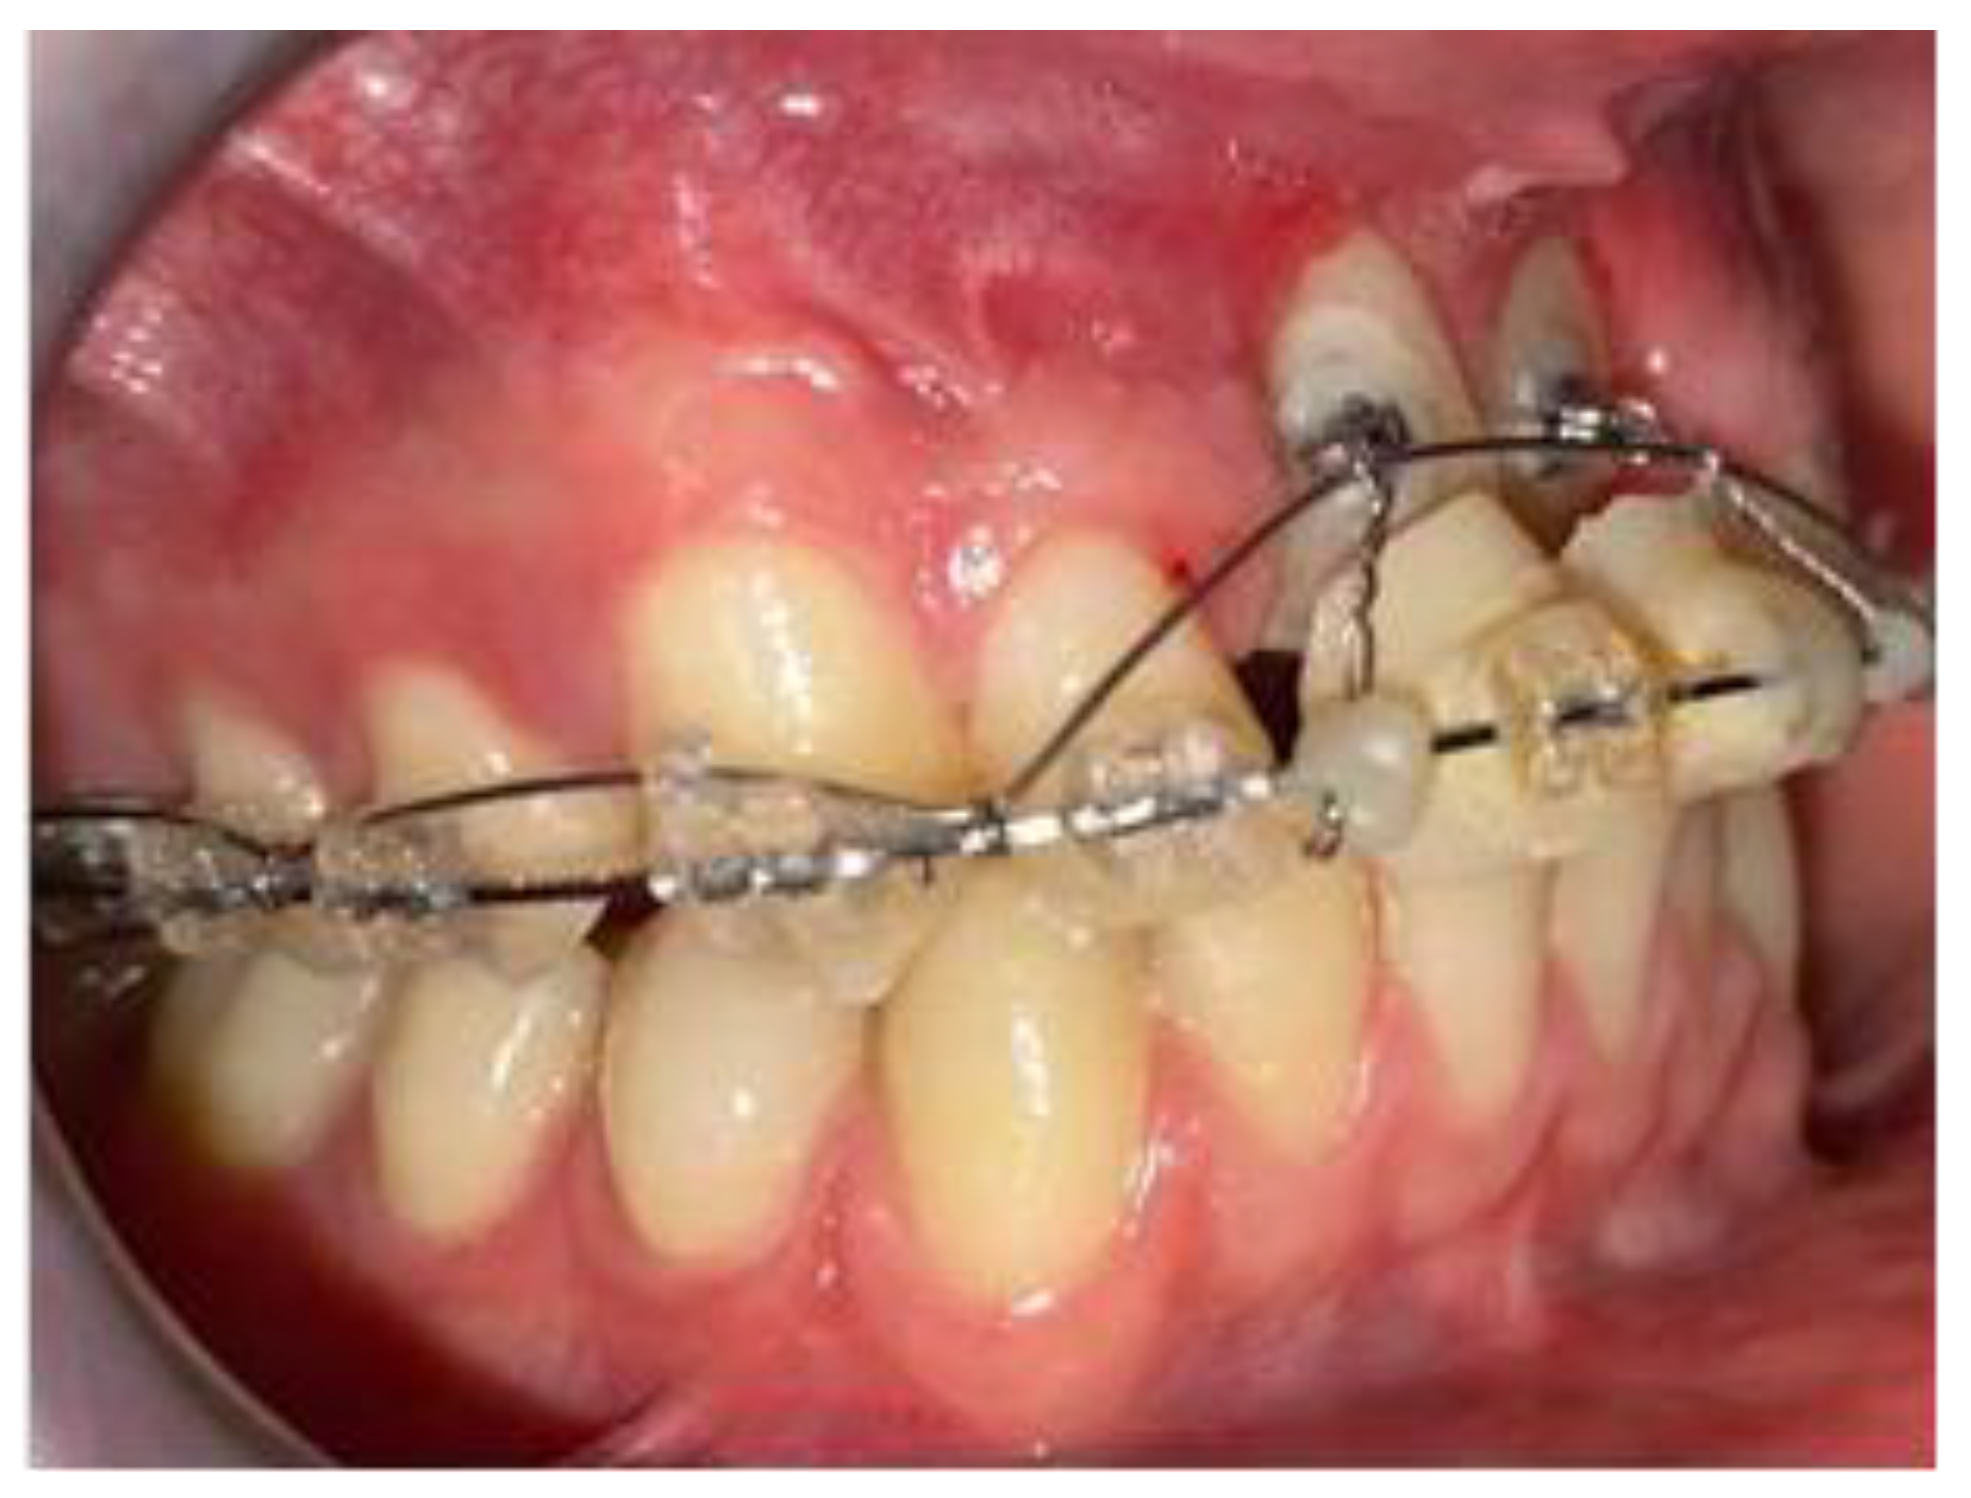

2. Case Report

2.1. Clinical History

2.2. Clinical Exams and Diagnosis

2.3. Therapeutic Plan